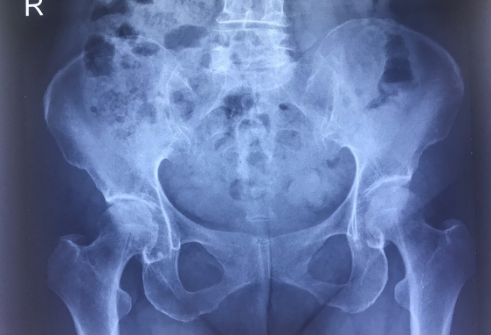

Trường hợp 1: Bệnh nhân T.T.T.Y sinh năm 1953, vào viện với lý do đau khớp háng trong 1 tháng gần đây, bệnh nhân được bác sỹ lâm sàng khám và cho chỉ định chụp Xquang khớp háng. Trên hình ảnh Xquang chỉ quanh sát thấy hình ảnh tổn thương đặc xương dưới sụn ổ cối và hẹp nhẹ khớp háng phải. Bệnh nhân được Bs. Trần Thị Thanh Xuân khoa CĐHA tư vấn chụp thêm phim cộng hưởng từ để chẩn đoán chính xác hơn.

Hình ảnh Xquang và MRI của bệnh nhân

Bệnh nhân được chẩn đoán hoại tử chỏm xương đùi phải giai đoạn II theo phân loại Arlet – Ficat. Với những tổn thương phát hiện sớm như thế này, bệnh nhân sẽ được điều trị nội khoa nhằm bảo tồn khớp háng.